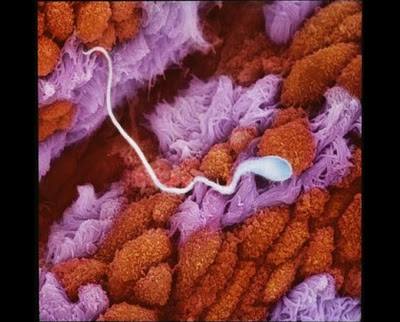

Սպերմատոզոիդն արգանդափողում

Ֆալոպյան փողը, որի միջով բեղմնավորված ձվաբջիջն անցնում է դեպի արգանդ: